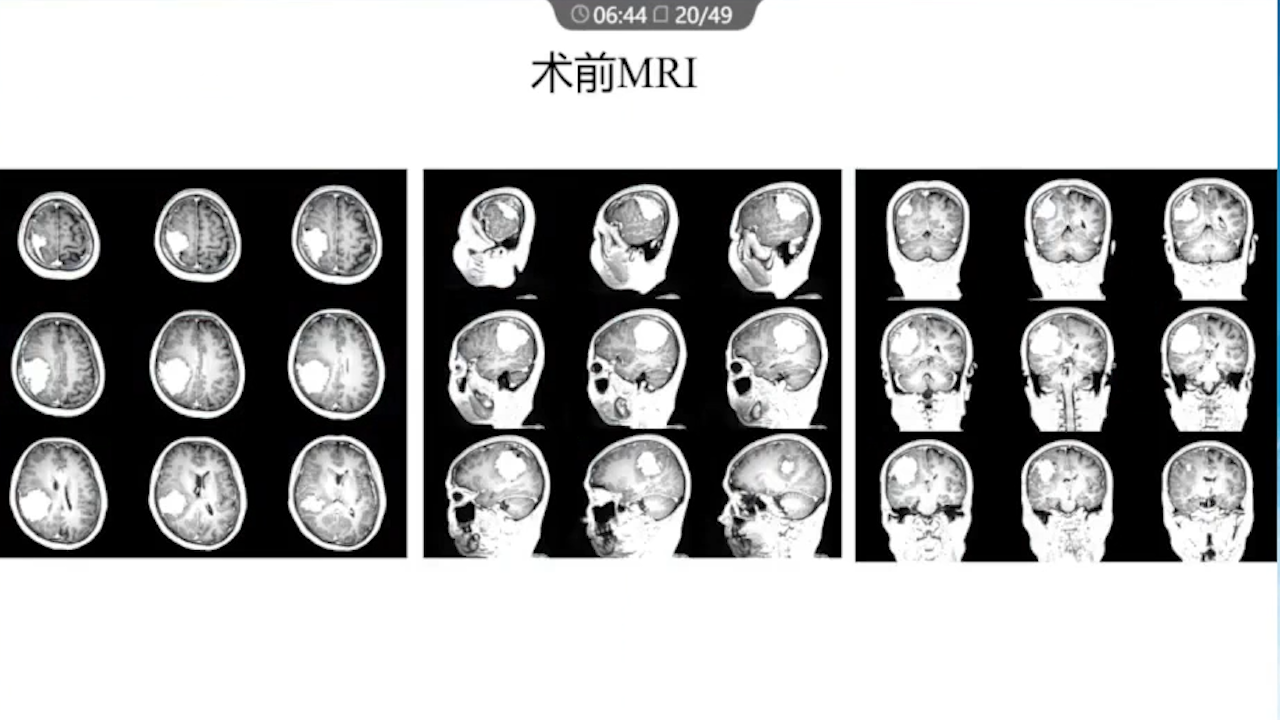

1、术前需要完善的影像学检查、多模态融合及神经导航以进行精确的肿瘤及静脉血管定位。

2、术中硬膜剪开及肿瘤切除时逐步接近功能区,在剪开硬膜前,可行B超定位桥静脉以防误伤,根据桥静脉的位置灵活调整硬膜的剪开方向。